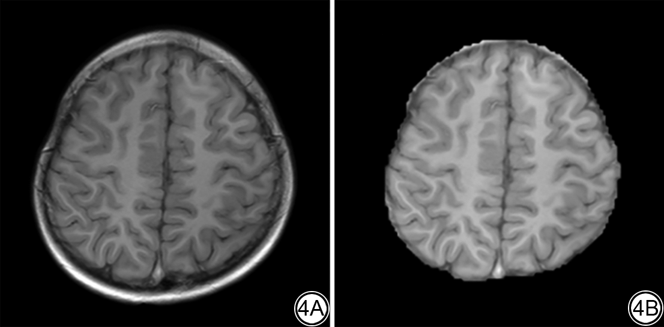

患儿因大脑发育不同导致实际扫描过程中存在扫描层数不一致的情况,从而无法满足模型单一输入尺寸的要求。本研究选取所有案例中最具有代表性的数量作为标准,对于未达到此层数的案例,对其首尾通过复制进行补充,以达到模型的输入要求。在本研究中,所有案例的层数统一为18,输入大小为512×512×18。然后通过HD-BET网络对脑部区域进行了分割,分割后的区域如图4所示[25]。最后对数据进行了归一化(0均值1方差)。